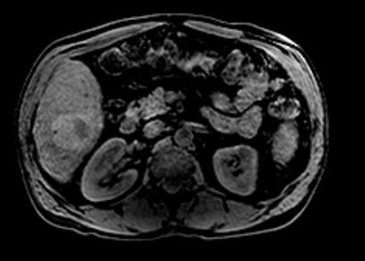

간 결절이란 간 조직 내에서 국소적으로 형성되는 작은 혹 형태 구조물을 말합니다. 주로 초음파, CT, MRI 검사에서 우연히 발견되는 경우가 많으며, 대부분은 양성 변화로 평가됩니다. 하지만 ‘간 결절 치료방법’을 고민하게 되는 이유는, 일부 경우 결절이 커지거나 악성 가능성이 있는 병변으로 의심되기 때문이죠.

간 결절의 종류에는 간 혈관종, 간낭종, 지방간 관련 혹, 간세포성 병변 등이 있습니다. 각 종류마다 환자 개개인의 상태에 따라 관리 방식이 달라질 수 있습니다. 예를 들어, 제가 관찰한 사례에서 한 지인은 간 혈관종이 약간 커진 상태로 발견되었지만, 병원 진료 후 단순 양성으로 판단되어 바로 치료하기보다는 생활습관 변화와 정기 추적검사를 택했어요.